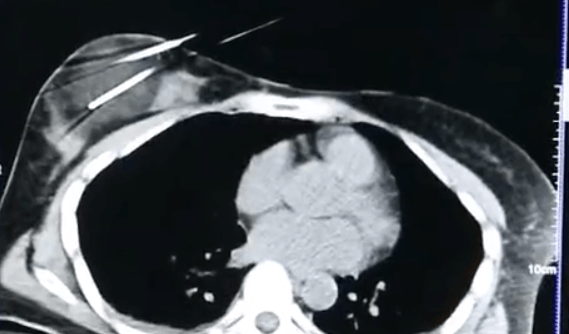

文章图片

刺激机体免疫系统

冷冻消融手术还可以降低周围组织受到损伤的风险,尤其是在处理膈肌以及心脏大血管附近的病变组织时,比其他类型手术更有优势 。 不仅如此,冷冻还会刺激机体的免疫系统,预防种瘤的局部复发 。